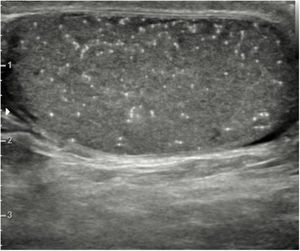

Cuando hay más de 5 microcalcificaciones presentes en una imagen del testículo, esto se denomina microlitiasis testicular. En la ecografía se ven como focos hiperecogénicos de 1 a 3mm sin sombra acústica posterior (Fig. 4). El hallazgo ecográfico de microlitiasis testiculares se encuentra en aproximadamente el 5% de los varones entre los 18 y 35 años. A pesar de múltiples estudios, la relación con el cáncer testicular no está claramente definida.